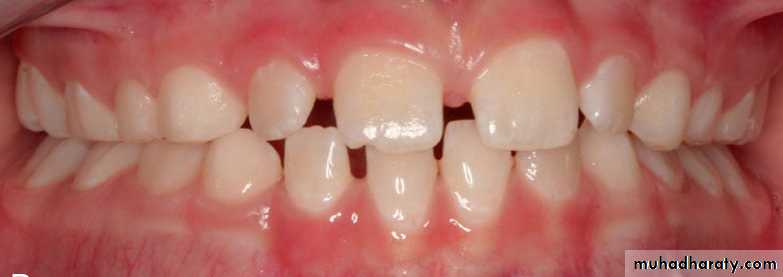

Posterior crossbite: is defined as a relationship in which one or more deciduous or permanent posterior teeth occlude in an abnormal buccolingual relation with their antagonists.

They may be unilateral or bilateral, maxillary or mandibular, buccal or lingual, dental or skeletal, and may be accompanied by lateral functional shift of mandible (especially in unilateral crossbites).

Palatal Posterior Crossbite: is the most common and refers to a condition where buccal cusps of one or more maxillary posterior teeth occlude lingual to buccal cusps of mandibular teeth.

Unilateral crossbite: may be associated with mandibular shift on closure or less frequently may result from true arch asymmetry.

Functional crossbite: Occlusal interference will lead to mandibular shift on closure resulting in unilateral posterior crossbite

Unilateral posterior crossbite with lateral shift may result from:

• Occlusal interferences from primary canine: there is normal occlusal relations at initial contact but in centric occlusion there is mandibular shift leading to unilateral crossbite.